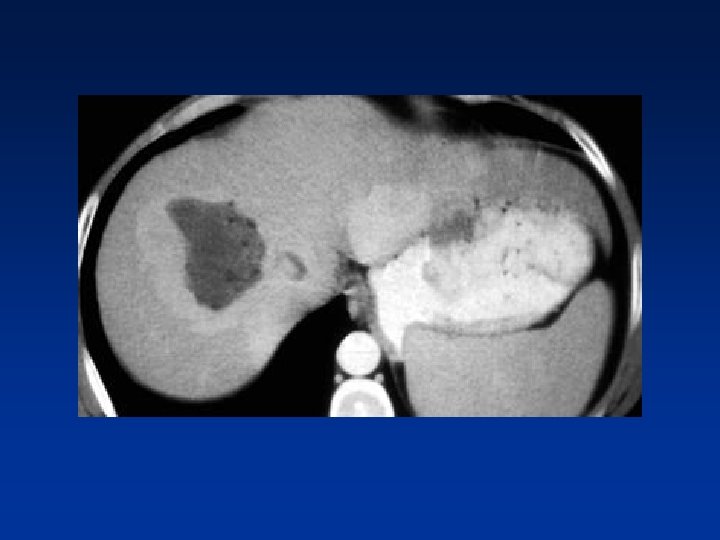

• Small cholangiocarcinoma not visible in portal venous phase , but seen as relative hyperdense lesion in the equilibrium phase.